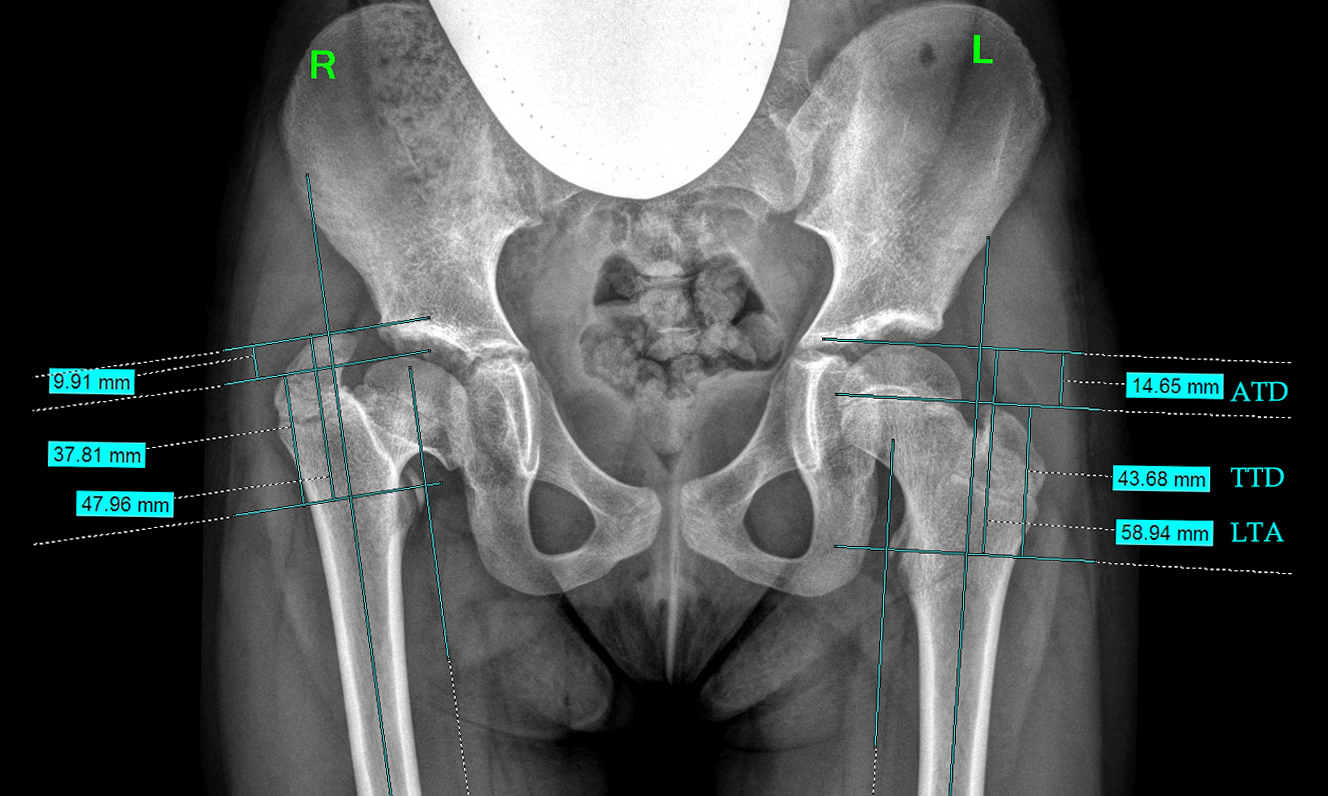

Несмотря на полиэтиологичность представленных групп пациентов, у всех обследуемых детей рентгенологические нарушения были сходными — показатель отношения верхушки большого вертела к центру головки бедренной кости принимал патологические значения. В рамках данной работы мы подробнее останавливаемся на индексах, характеризующих изменения роста большого вертела относительно головки и шейки бедра. Для уточнения динамики изменений рентгенологических показателей проксимального отдела бедренной кости были проанализированы цифровые рентгенограммы 56 обследованных больных (112 суставов), выполненных с соблюдением правильного масштабирования, в том числе при помощи калибровочного объекта для получения корректных данных (рис. 6).

Рис. 6. Пример рентгенометрического анализа показателей, характеризующих изменения положения большого вертела относительно головки и шейки бедра. ATD — артикуло-трохантерная дистанция; TTD — межвертельное расстояние; LTA — расстояние от малого вертела до верхнего полюса головки бедра

Рис. 1. Показатели, характеризующие соотношения головки бедра и большого вертела во фронтальной плоскости (McCarthy J.J., Weiner D.S., 2008, с изменениями) [12]. ATD — артикуло-трохантерная дистанция; TTD — межвертельное расстояние; LTA — расстояние от малого вертела до верхнего полюса головки бедра

Этими показателями являлись:

а) артикуло-трохантерная дистанция (articulo-trochanteric distance, ATD) — расстояние от верхушки большого вертела до верхнего полюса головки бедра (мм);

б) межвертельное расстояние (trochanter-to-trochanter distance, TTD) — расстояние от верхушки большого вертела до середины малого вертела вдоль линии, параллельной анатомической оси бедренной кости. Показатель отражает рост большого вертела и не зависит от роста эпифиза;

в) расстояние от малого вертела до верхнего полюса головки бедра (lesser trochanter-to-articular surface distance, LTA). Показатель отражает рост эпифиза и шейки бедренной кости и не зависит от роста большого вертела.